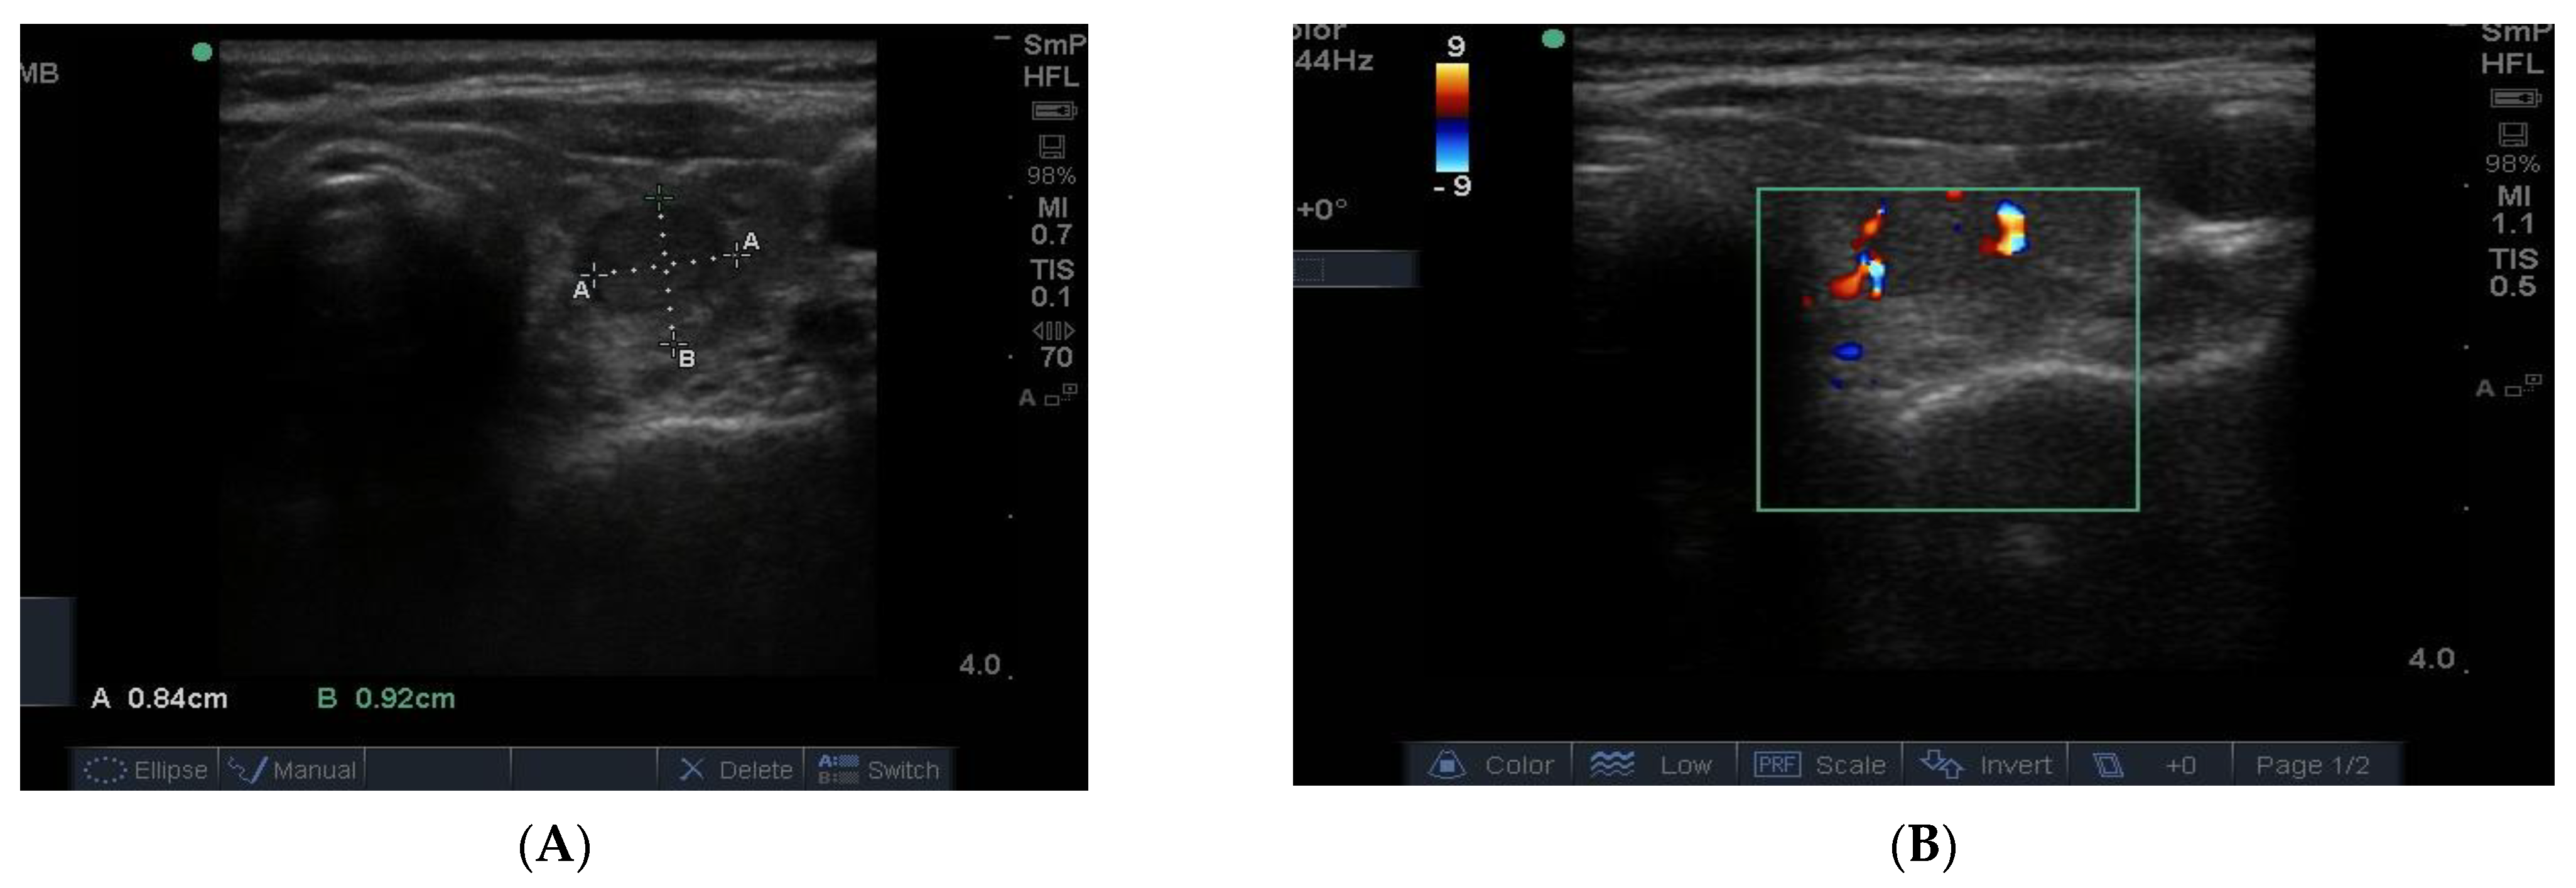

In Figure 10 is shown matching images of a benign nodule without (A) and with (B) blood flow in the halo around the nodule.

Figure 10. A small 8 mm benign nodule in the left thyroid lobe shown as an ultrasound image (A) and with surrounding vascularity in (B).